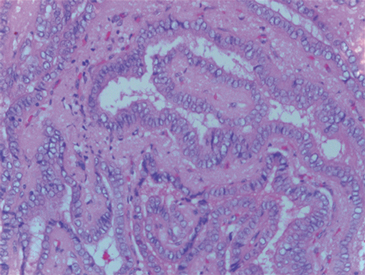

Una paciente de 61 años consultó al servicio de ginecología por un cuadro de hemorragia uterina anormal, para este momento la paciente no refería ningún otro síntoma. Dentro de los estudios solicitados la ecografía transvaginal reportó una imagen quística de 3 cm con múltiples septos y papilas en su interior en el ovario derecho que posteriormente fue caracterizado mediante una tomografía de abdomen y pelvis (Figura 1). Cuatro meses después de haber consultado, y con la sospecha de un carcinoma de ovario fue llevada a cirugía donde se realizó resección de ambos ovarios y útero y no se encontró compromiso macroscópico más allá del ovario; no presentó complicaciones asociadas al procedimiento. En la evaluación de patología describen en el ovario derecho un foco de 0,5 x 0,6 cm de un carcinoma papilar variedad folicular de tiroides en un struma ovarii (Figura 2).

Figura 2. Histología del foco de carcinoma papilar de tiroides en ovario derecho. Folículos de aspecto dilatado y quístico con coloide en su interior, con otras áreas de estructuras foliculares revestidas de células cilíndricas con núcleos densos y otros de cromatina clara, algunos en grano de café con variación en el tamaño, algunos superpuestos. Las estructuras foliculares están adosadas entre sí y algunas están sumergidas en tejido fibroso; hallazgos correspondientes a un foco de carcinoma papilar patrón folicular en un struma ovarii.